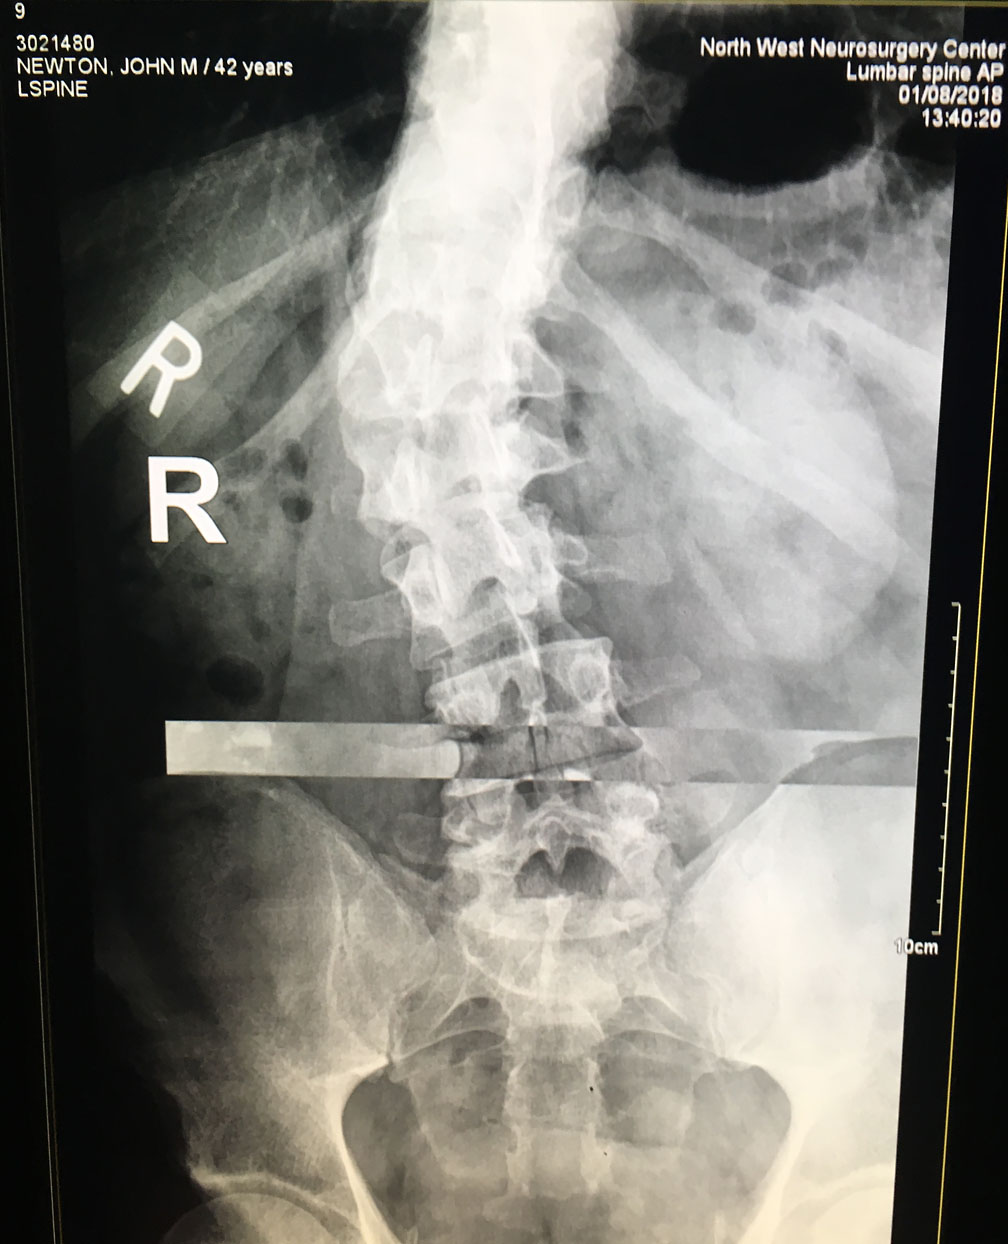

My latest target for medical help is my spine. My back resembles a melted candy cane and my peppermint stripes are all twisted, skull to pelvis. I’m in nerve pain daily up and down my back. Many times I can handle the pain with grace. Many times I cannot. So I wanted to know from an expert what can be done — beyond physical therapy — to alleviate my pain.

The visit with Dr. Luke Knox went great. He sent a lot of time talking to us, examining me, and showing us the 15 X-Rays they took of my back today, along with a recent MRI. I’ve found few doctors who will take ample time to attend to their patients and answer questions. A frustration I have with modern doctors is their tendency to ask 10 questions, hold up your arm, and then guess at what’s wrong with you. They see you for eight minutes, charge you $400 and leave you feeling disrespected in some way. But Dr. Knox was wonderful. Even when he repeatedly said, “That doesn’t look good.”

My right hip is half an inch lower than my left hip. This is degenerative and has come from the gradual worsening of my spine. I will need to try a shoe extension (like a booster seat inside my right shoe) to level my hips. This will relieve some pressure on my lower and mid back and — hopefully — relieve some pain. But I will probably limp for a while until I get used to the change in leg length.-